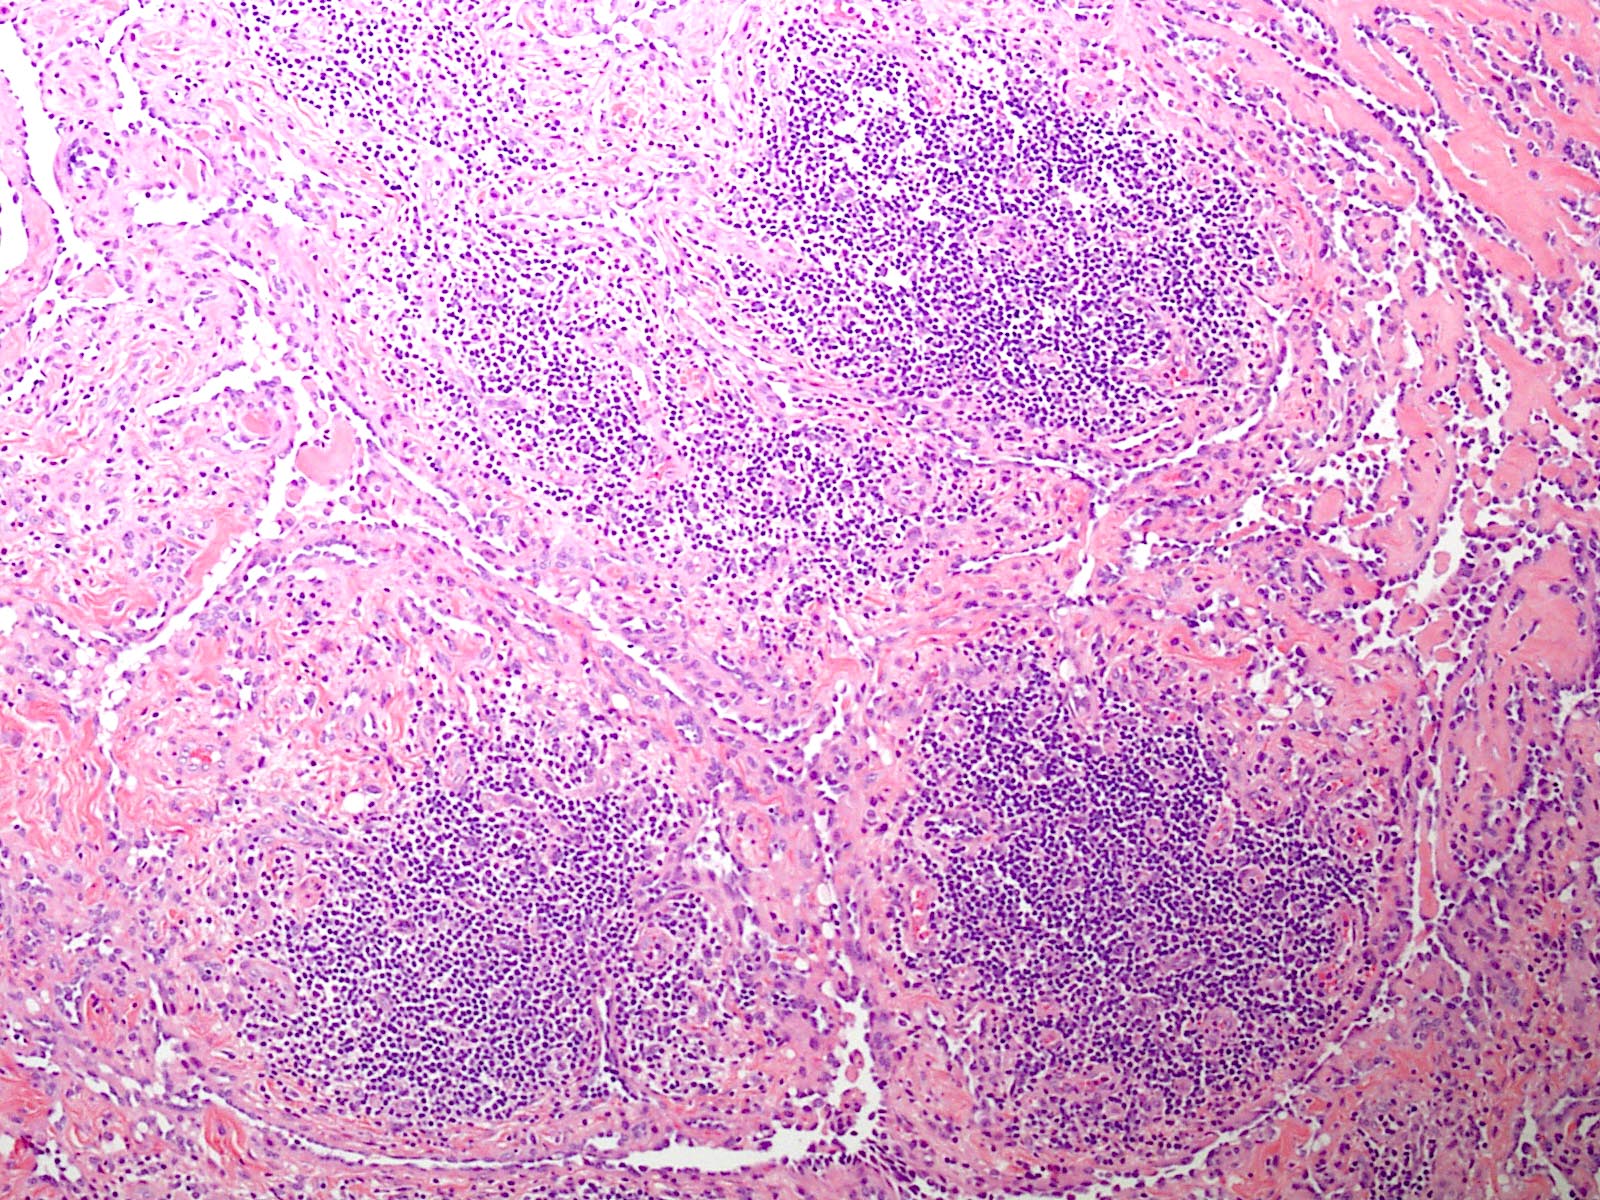

Microscopic (histologic) description

- Poorly circumscribed lesion, infiltrating dermis and subcutis with dissecting planes (Int J Clin Exp Pathol 2010;3:528)

- Composed of elongated arborizing vascular channels that resemble rete testis, hence the name

- Lesional stroma is fibrotic and shows lymphoid infiltrate (J Med Case Rep 2021;15:69, Int J Clin Exp Pathol 2010;3:528)

Microscopic (histologic) images

E. Retiform hemangioendothelioma. The photomicrograph shows a vascular lesion with retiform vessels lined by a single layer of endothelial cells with hobnailing. A lymphoid aggregate is also present. Answers B - D are incorrect because other characteristic essential features of any of the given options, except atypical vascular lesion, are not seen here. Answer A is incorrect because the clinical scenario is not appropriate for a diagnosis of atypical vascular lesion. Therefore, the correct diagnosis is retiform hemangioendothelioma.